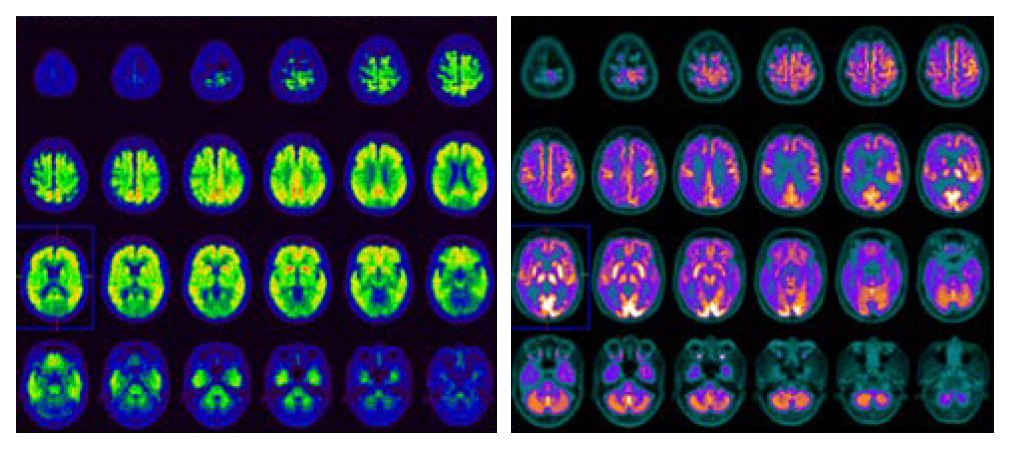

PET/CT and Alzheimer’s Disease

Positron Emission Tomography (PET) scan is valuable to show and quantify the cellular activities and the

distribution of functional molecules in the brain. PET/CT

imaging examinations available in HKSH utilise multiple

tracers to aid the diagnosis of Alzheimer's disease and

the other causes of dementia:

• 11C-Amyloid and 18F-Tau PET/CT scans measure

abnormal accumulation of amyloid and tau proteins

in the brain serve as diagnostic indicators for

Alzheimer’s disease

• 18F-FDG PET/CT scan measures glucose metabolism

in the brain which is useful for differentiating

Alzheimer’s disease from other causes of dementia

Early Alzheimer's disease can be detected by PET/CT

scan before onset of signs and symptoms. Neurologists

can guide patients on measures to reduce the impact of

future cognitive decline.